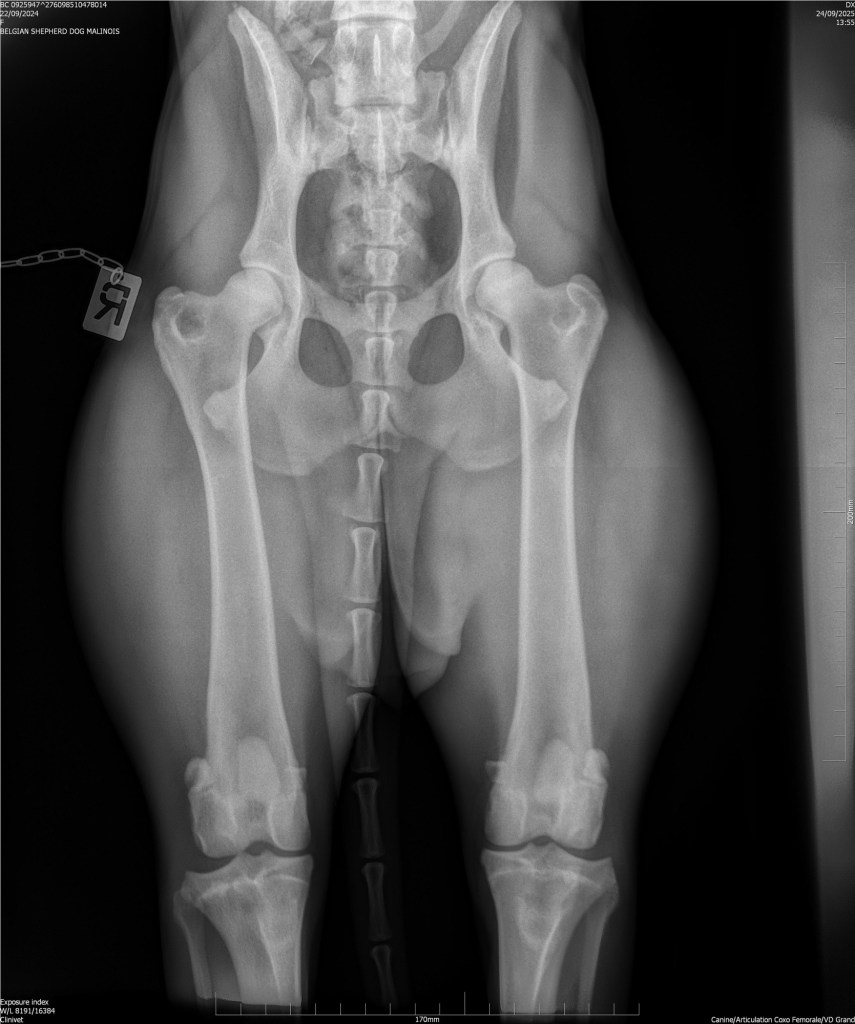

Hips 2/3